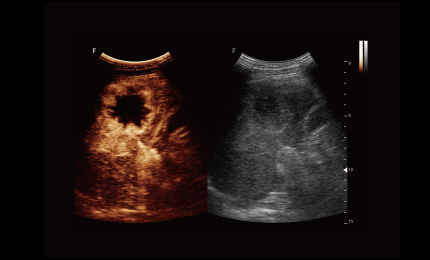

Technologia obrazowania ultrasonograficznego z inwersją impulsów i kontrastowaniem pozwala dokładnie wyodrębnić drugi harmoniczny kontrastowych mikropęcherzyków, co umożliwia uzyskanie obrazowania z wysokim stosunkiem kontrastu do tkanki oraz zapewnia bardziej szczegółową diagnozę kliniczną.